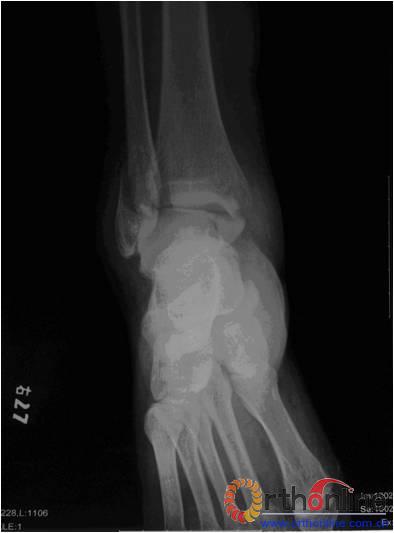

本组患者均获得随访,随访时间为6~12个月,平均9个月。所有患者切口I期愈合。随访采取美国足踝外科协会评分 [American Orthopedic Foot and Ankle Society (AOFAS) hindfoot and ankle scores]评定踝关节功能(76~94分,平均87.3分)。随访患者均拍摄双侧踝关节正侧位X线片(图3),并对其进行测量。X线示:术后患侧下胫腓间隙平均为3.8mm(3~5mm)。本组患者中未发生术后下胫腓关节间隙再次增宽以及骨间缝合线再次手术取出。无感染,血管神经损伤及内固定失败等并发症。

a

b

3 a. 术前患者踝关节X线片,可见下胫腓关节间隙增宽;b. 术后患者踝关节X线片,未见下胫腓关节分离现象